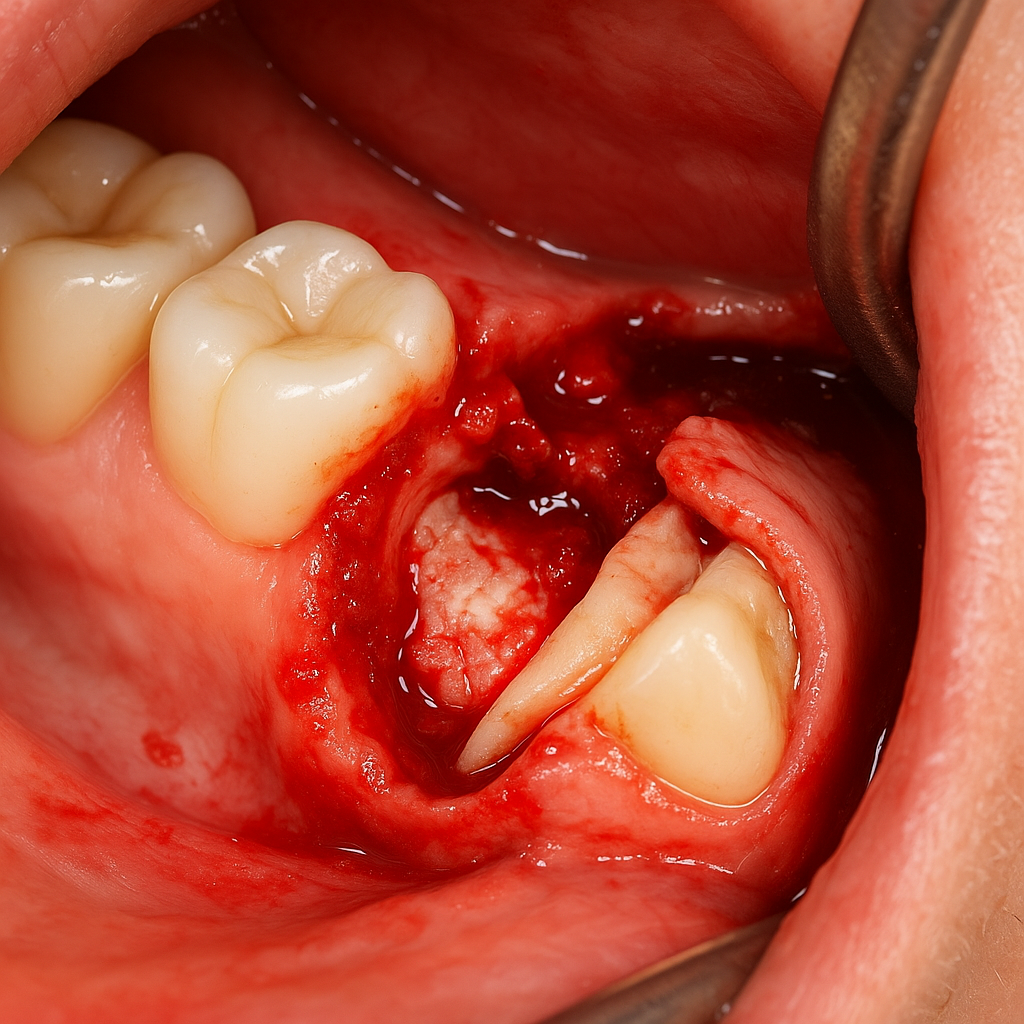

۱. جراحی دندانهای نهفته و نیمهنهفته

یکی از شایعترین دلایل مراجعه به جراح فک و صورت، دندان عقل نهفته است. این دندانها معمولاً در فک پایین یا بالا بدون اینکه بهطور کامل بیرون بیایند، زیر لثه و حتی استخوان گیر میکنند. در برخی موارد حتی به عصب فکی تحتانی یا سینوس ماگزیلاری بسیار نزدیک میشوند.

مواردی که فقط متخصص باید انجام دهد:

- دندان عقل با ریشه خمیده یا چندتکه

- نزدیکی یا تماس مستقیم با عصب فکی تحتانی (IAN)

- نیاز به برداشتن بخشی از استخوان یا شکافتن بافت نرم

- دندان عقل افقی یا مایل به ریشه دندان مجاور

در چنین مواردی، هرگونه خطای جراحی توسط دندانپزشک عمومی میتواند منجر به فلج شدن لب، بیحسی دائمی فک یا آسیب جدی به بافتها شود.